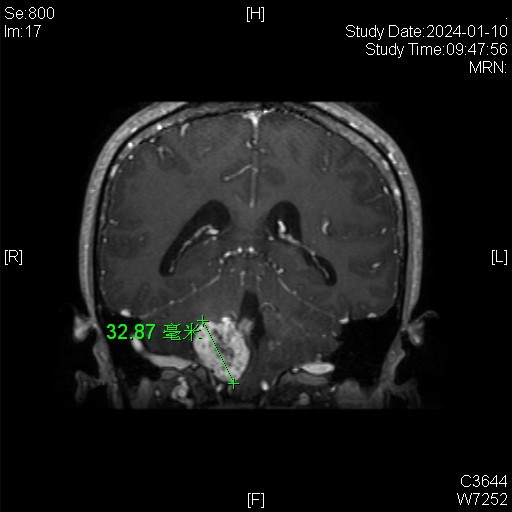

病例特点:

女性患者,26岁,因“间断性头晕1月余。”于2024-01-08入院。

患者1月余前感冒后出现头晕,伴头痛,伴恶心、呕吐。

家族史:患者母亲诊断多发小脑血管母细胞瘤,在我院手术治疗。

体检发现肝脏多发囊肿、右肾囊肿、胰腺多发囊肿。

诊断:延髓血管母细胞瘤

von Hippel-Lindau综合征